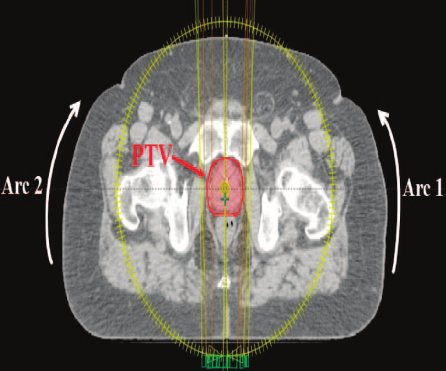

Volumetric modulated arc therapy(VMAT) or Rapid arc is an advanced form of IMRT that delivers a precisely sculptured 3D dose distribution with a 360 degree rotation of the gantry in single or multiple arc treatment.